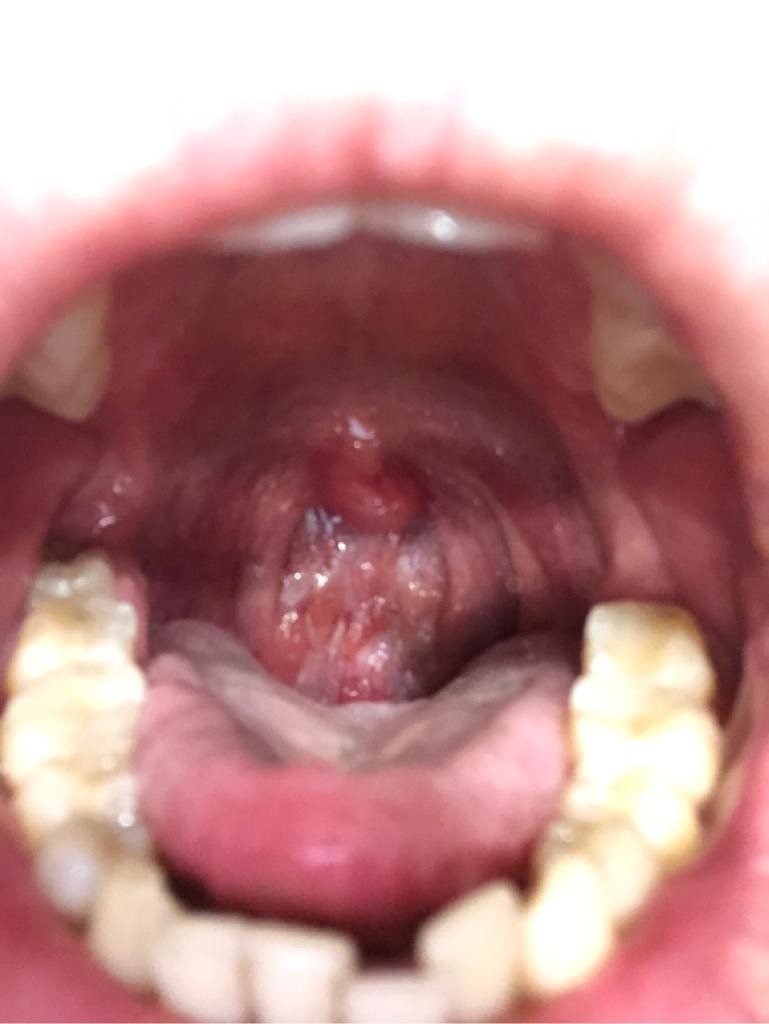

Здравствуйте, месяц назад у меня заболело горло. Я стал полоскать горло календулой, а также использовал спрей тандум верде и рассасывал пастилки анти ангин, лизобакт. Обычно при такой схеме у меня горло всегда проходило. Но сейчас оно продолжало болеть. Пропил курс Амиксина. Спустя неделю горло не проходило и я стал опрыскивать горло Мирамистином. Горло не проходило, а после мирамистина появилась ужасная сухость в горле. Особенно, когда просыпался утром. После отмены мирамистина и приема Имудона сухость стала меньше. Сейчас прошел месяц, горло до сих пор беспокоит. Не сказал бы, что оно болит, как в начале, глотать не больно, но есть дискомфорт, небольшая сухость, как будто что то мешает. Кашля все это время не было, температура все это время была в норме, насморк отсутствовал. Чувствую себя хорошо. При этом на горле смущают красные бугорки. Фото прилагаю. Подскажите, может ли это быть бактериальный фарингит? Надо ли сдать мазок на микрофлору? Оправдан ли будет прием антибиотиков?

По фото острый фарингит.

Непременно стоит сдать мазок из глотки на флору и антибактериальную чувствительность.